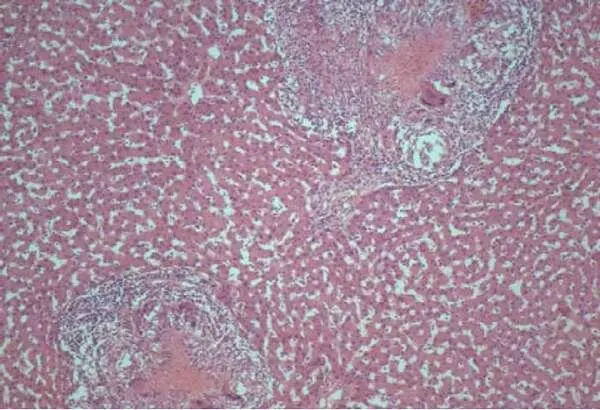

Рисунок 21 – Туберкулезный гепатит при ВИЧ–инфекции: множественные гранулемы с обширной зоной казеозного некроза. Окраска гематоксилином и эозином. Х200.